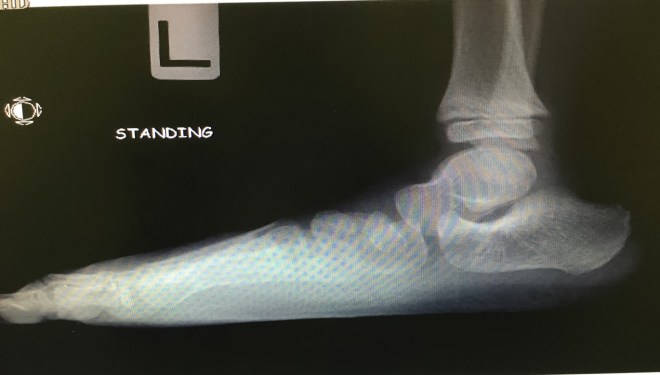

Flat Feet (Copyright Kapil Bakshi)